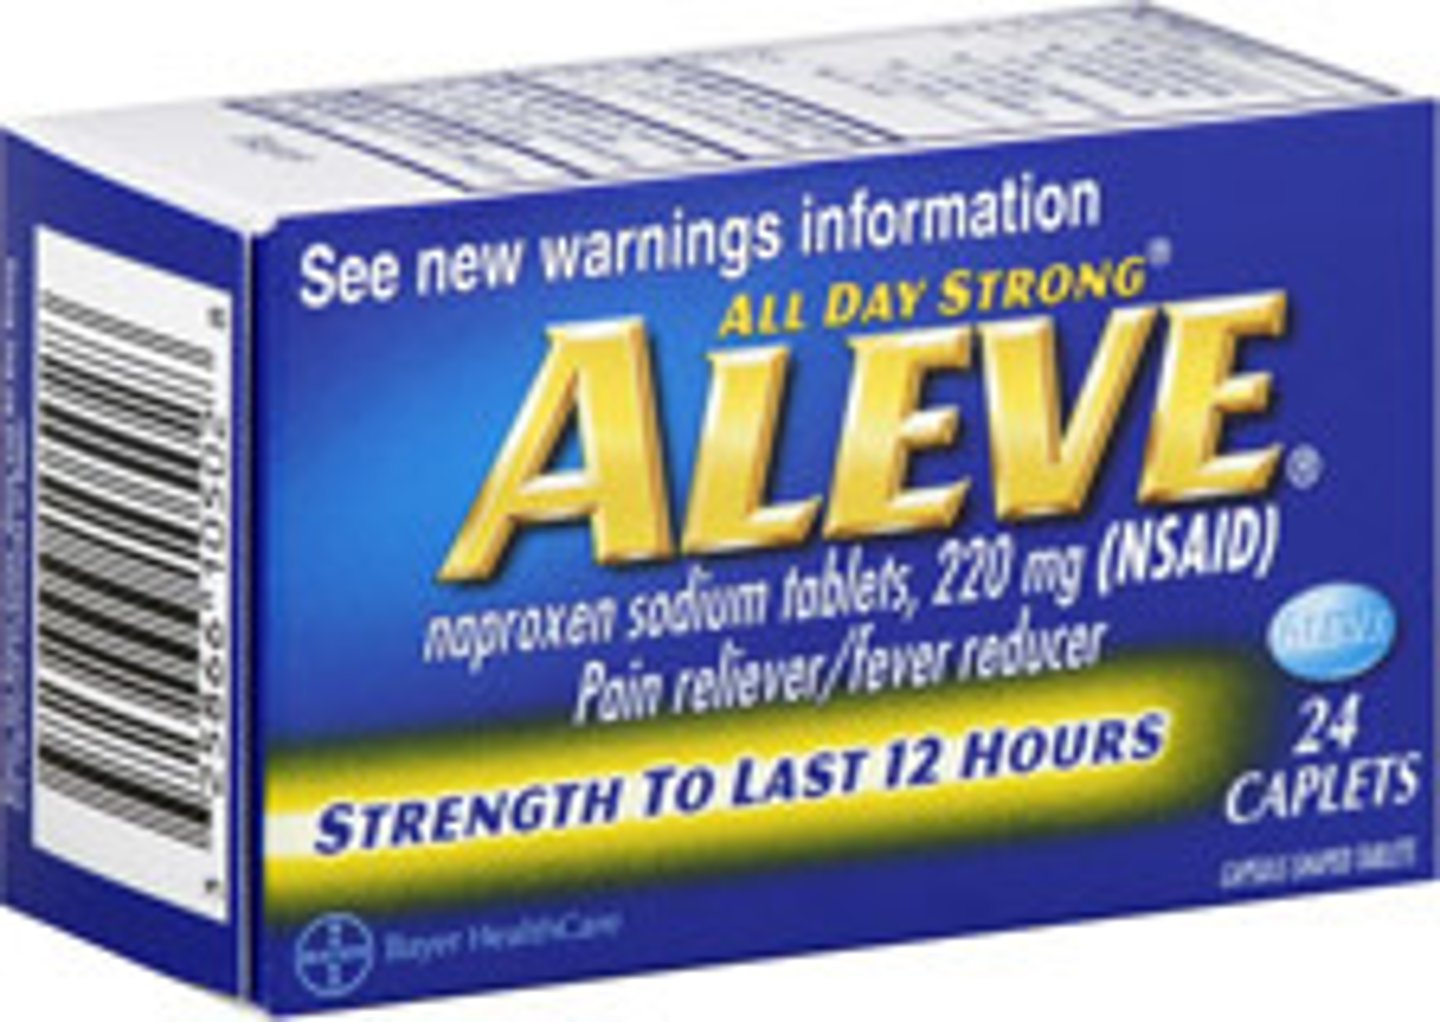

Naproxen

Brand: Aleve

Class: NSAID

Drug Interactions:

1) Can lead to higher Lithium Levels

2) Can lead to higher Methotrexate Levels

Interaction: Increased Risk of Bleeding with Coumadin

Indication: Pain/Inflammation Relief

Schedule: OTC & NCLM (strength)